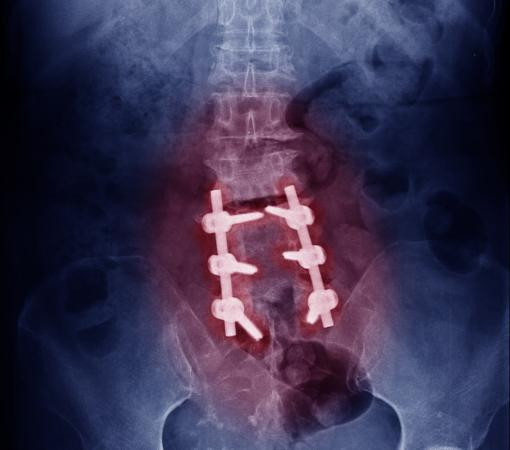

The damaged vertebra or disc is removed.

A bone graft is placed to promote fusion.

Screws or rods may be used to provide support.

The bones naturally fuse over time, creating a stable structure.